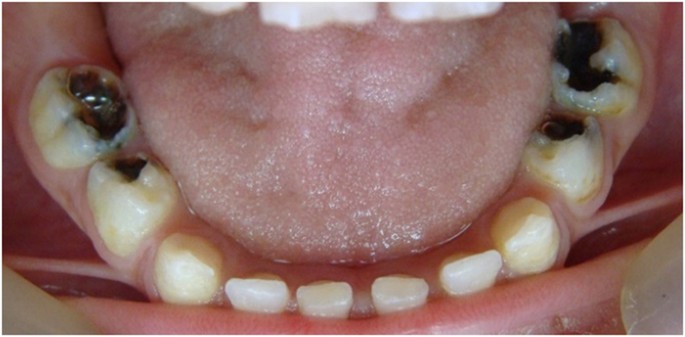

The teeth in the formocresol group had a clinical success rate of 100% at 1 month, 94.4% at 6 months and 88.2% at 12 months (Figures 2,3,4,5,6,7,8). The teeth in the propolis group had a clinical success rate of 94.7% at 1 month, and 88.2% at 6 and 12 months. The thymus vulgaris group had a clinical success rate of 94.4% at 1 month, and 94.1% at 6 months and 12 months follow-up. Statistical analysis of the data, using Friedman’s test, revealed no statistically significant differences between the three groups at all follow-up appointments (Table 1).

The teeth in the formocresol group had a radiographic success rate of 95.0% at 1 month, 81.2 at 6 months and 73.3% at 12 months. The teeth in the propolis group had a radiographic success rate of 94.7% at 1 month, 81.2% at 6 months and 73.3% at 12 months. The thymus vulgaris group had a radiographic success rate of 94.4% at 1 month, and 87.5% at 6 and 12 months. Statistical analysis of the data, using Friedman’s test, revealed no statistically significant differences between the three groups at all follow-up appointments (Table 2).